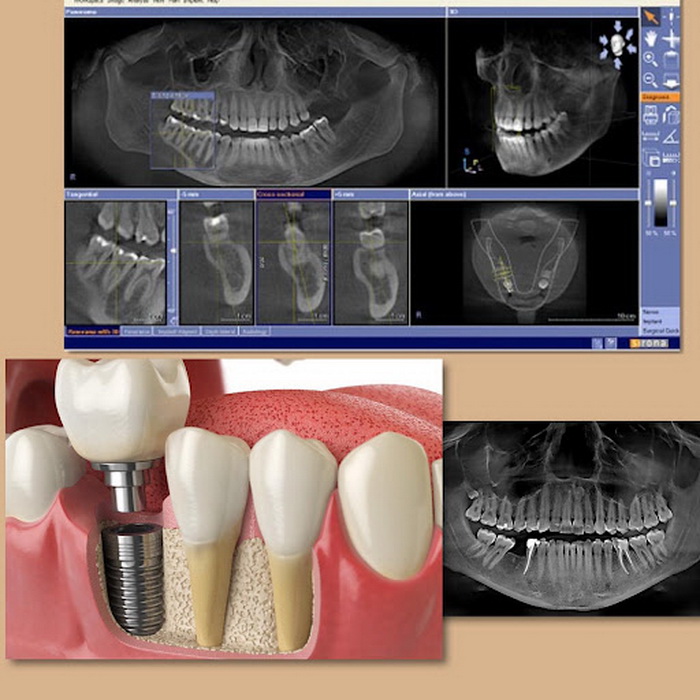

Подумайте о разнице между старым методом и новым. Раньше всё держалось на мастерстве и глазомере хирурга: слепки, примерки, риск человеческой ошибки. Это как кроить дорогой костюм без точной выкройки. Цифровой протокол — это индивидуальный пошив по скану тела. Всё начинается с компьютерной томографии (КТ) и внутриротового сканирования. На экране возникает не просто изображение, а 3D-модель вашей челюсти со всеми нервами, пазухами, плотностью кости. В этой виртуальной реальности хирург планирует положение каждого импланта с ювелирной точностью — туда, где кость наиболее плотная и прочная, под идеальным углом для будущей нагрузки. Затем программа создает хирургический шаблон — индивидуальную каппу с направляющими каналами. Во время операции он надевается на зубной ряд, и сверло физически не может отклониться от запланированного пути. Это сводит травму тканей к абсолютному минимуму.

Острая боль — это следствие грубого вмешательства и длительного заживления. Точность цифрового шаблона превращает установку импланта в процедуру, больше похожую на микрохирургию: быстро, атравматично, предсказуемо. Но ключевое слово — предсказуемость. Пациент ещё до первого разреза видит на экране финальный результат: как будет стоять титановый корень и как будет выглядеть будущая коронка. Это снимает главную тревогу — страх перед неизвестностью. Более того, цифровые технологии позволяют моделировать коронку, которая будет иметь не гладкую, а слегка текстурированную поверхность, как у натуральной эмали. Это важно для правильного прикуса и того самого, почти забытого, ощущения пищи.